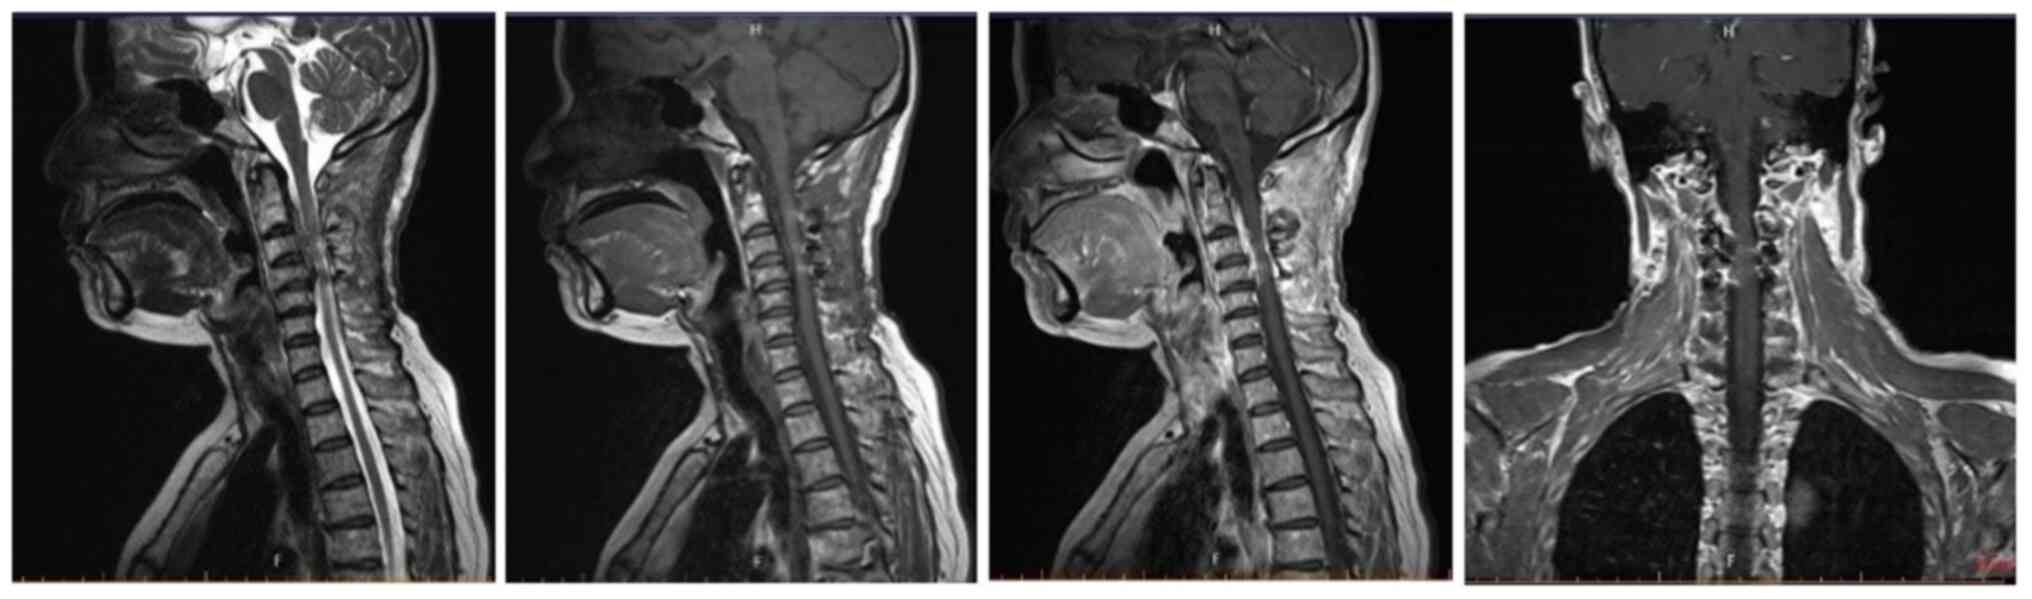

The day after admission, a cervical spine CT showed a mixed density lesion in the spinal canal and spinal stenosis at the posterior edge of the cervical 3–4 pyramid (Fig. 1). A total of 3 days after admission, head and neck CT angiography showed no significant abnormalities (Fig. 2); on the same day, cervical spine enhanced magnetic resonance imaging (MRI) showed a space-occupying lesion in the spinal canal at the C2-4 level (Fig. 3). A total of 11 days after admission, cervical intraspinal tumor resection was performed under general anesthesia, during which the posterior arch of the atlas, C2-C4 spinous process and lamina were exposed, and the bilateral laminae of C2-C4 were grooved with a burr to completely remove the lamina including the C2-C4 spinous process. The lesion broke through the dura mater and grew into the right C3-C4 intervertebral foramen, and the base of the tumor was located in the dura mater, which was firm in consistency, calcified, poorly circumscribed and rich in blood supply. A piecemeal resection of the tumor was performed, the boundary of the lesion on the surface of the spinal cord was carefully separated, part of the C3-C4 facet was abraded, the intervertebral foramen was explored, and the intraforaminal lesion was subtotally removed. Finally, the patient underwent fixation and reduction surgery for the C2-C4 lamina. Postoperative pathology showed cervical spinal meningioma with local hot spot mitotic figures of ~3/mm, morphology consistent with atypical meningioma (World Health Organization grade II) (6), accompanied by bone tissue invasion, and no neoplastic necrosis or spinal cord invasion (Fig. 4). Immunohistochemical results (Fig. 5) were as follows: Broad spectrum cytokeratin (focal weak data not shown), epithelial membrane antigen (Fig. 5C), glial fibrillary acidic protein (data not shown), progesterone receptor (Fig. 5B), vimentin (data not shown), H3K27me3 (data not shown), STAT6 (data not shown), somatostatin receptor type 2 (Fig. 5A), S-100 (data not shown) and Ki-67 (~2%, data not shown). Immunohistochemistry was performed according to a previously described protocol (7). A total of 12 days after admission, cervical spine CT showed satisfactory tumor resection (Fig. 6). The patient was treated with mannitol (125 ml/time, tid), methylprednisolone (500 mg/time, qd) and methylcobalamin (0.5 mg/time, tid) after surgery. Eventually, the condition of the patient improved and they were discharged.

Figure 3.

Cervical spine enhanced magnetic resonance imaging 3 days after initial admission.